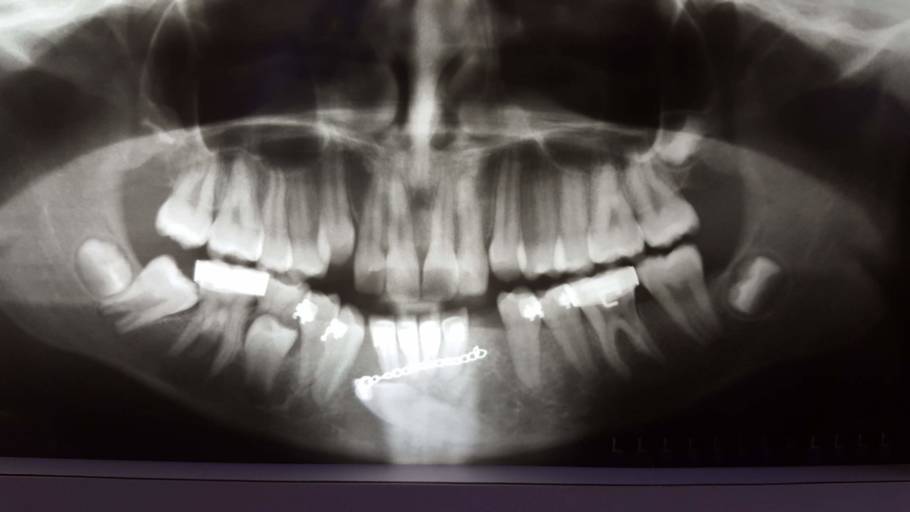

How should I fix the problem with my transmigrated mandibular canine?

I have a transmigrated mandibular canine. It is very far into my jaw. My orthodontist decided to attach a button onto the tooth, run a chain through my gums and attach it to my 2nd furthest back tooth. This constant pressure is moving the tooth into poison. Right now my midlines are so messed up to make room for this tooth to come in. We recently found out that the 2nd furthest back canine (which should be an anchor) is actually moving forward and the transmigrated tooth is acting as an anchor. I had surgery in January of 2018 and they removed some of my jaw to attach the button to my tooth. Now, they want to do surgery again and remove the transmigrated tooth. Then, they want to move forward one of my teeth and shave it down so it looks like a canine so I have a gap in the back instead of the front. What do you recommend?